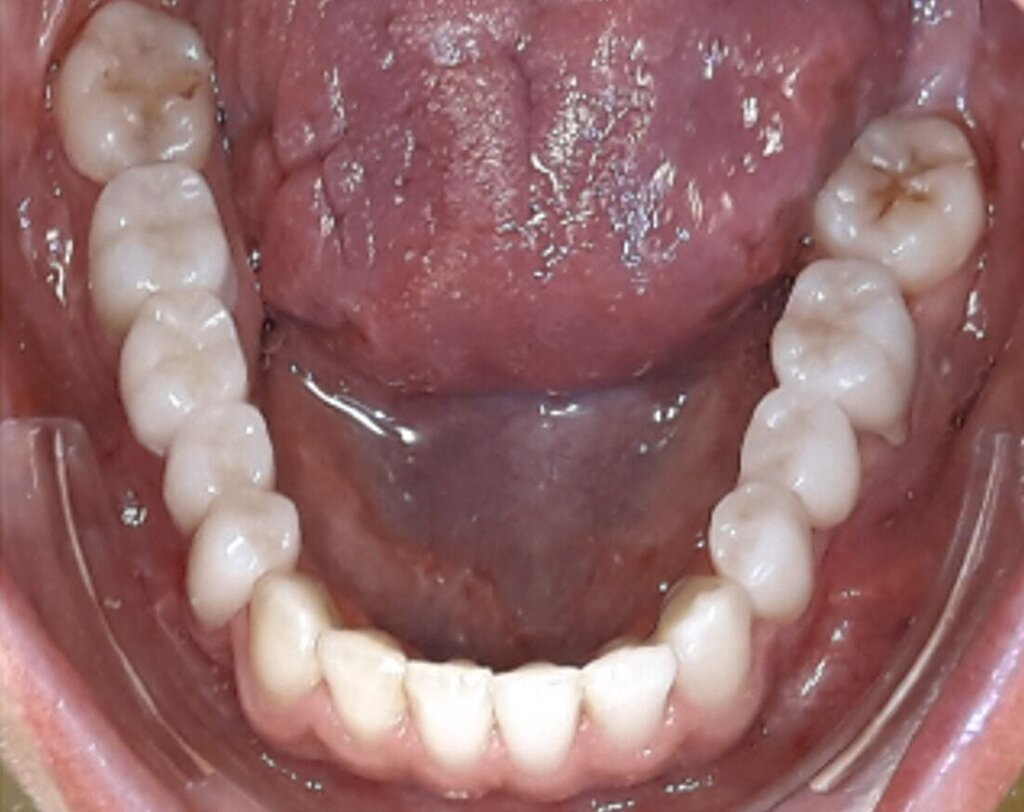

Ein 25-jähriger Patient stellte sich mit dem Wunsch nach Optimierung seines Erscheinungsbildes und seiner Kaufunktion in der kieferorthopädischen Praxis vor (Abbildung 1). Klinisch zeigten sich eine Angle-Klasse-III-Verzahnung mit einer 3/4 Prämolarenbreite Mesialokklusion beidseits und ein zirkulärer Kreuzbiss von 18–12/48–41 und 21–28/31–37. Es lagen ein negativer Overjet von -6,7 mm und ein Overbite von 5,1 mm vor. Eine Mittellinienverschiebung wurde sowohl im Oberkiefer – mit einer Abweichung von 4 mm nach rechts – als auch im Unterkiefer – mit einer Abweichung von 3 mm nach links – diagnostiziert (Abbildungen 2 und 3).

Aufgrund einer hohen Kariesanfälligkeit und einer klinisch floriden Parodontitis waren bereits mehrere Zähne des Patienten extrahiert worden, darunter 16, 11, 25, 38, 35, 45 und 46. Die mesiale Kippung und Aufwanderung der angrenzenden Zähne ließ vermuten, dass der Zahnverlust zeitlich weiter zurücklag. Aufgrund der reduzierten Langzeitprognose des Zahnes 11 entschieden wir uns gemeinsam mit dem Patienten für eine Ausgleichsextraktion des Frontzahns.

Der Hauszahnarzt versorgte die Zähne 12 und 22 mithilfe eines zuvor erstellten Wax-ups jeweils mit CAD/CAM-hergestellten Einzelkronen. Die Schaltlücken im Unterkiefer wurden mit Brücken geschlossen. Abschließend wurden im Unterkiefer ein festsitzender Retainer (33–43) eingesetzt und in beiden Kiefern zusätzlich Miniplastschienen zur Retention verwendet (Abbildungen 5 bis 7).